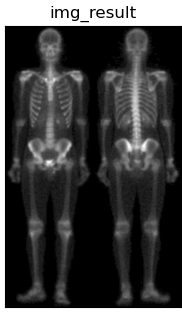

| 由于图像灰度范围窄,整体偏暗,在此使用灰度幂变换扩展灰度范围,使得更符合人眼观察。 |

根据幂律(伽马)变换基本形式:

\gamma=0.5,c=1

γ=0.5,c=1,最终得到的混合增强图像如下,可以看出人体的外形轮廓清晰,手腕,手掌等骨骼细节由人眼也可观察到。

| 最终将各结果进行对比显示 |